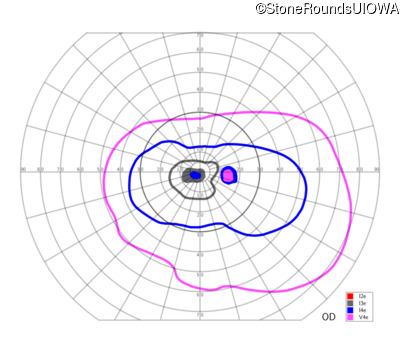

Congenital Stationary Synaptic Dysfunction (IA2g)

Congenital Stationary Synaptic Dysfunction (IA2g)

| Age at visit: 33 years |

| Age at visit: 35 years |

| Age at visit: 37 years |